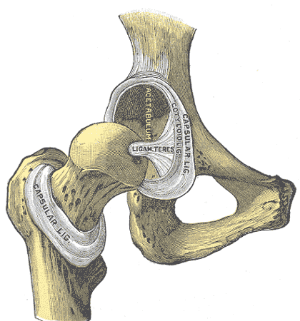

Anatomy

The ligamentum teres is a triangular band made of 1-3 bands or bundles attaching from the acetabulum to the fovea (Bardakos & Villar, 2009). It's been described as similar to the anterior cruciate ligament (ACL) as both are intra-articular with a bundled appearance and similar ultimate load to failure. However, ligamentum teres does not have fibrocartilaginous attachments, it has more nociceptors than the ACL, there's no experimental data on the bundles, and in general, the anatomy is poorly researched (Bardakos & Villar, 2009).

Anatomy of Ligamentum Teres. Bardakos & Villar (2009)